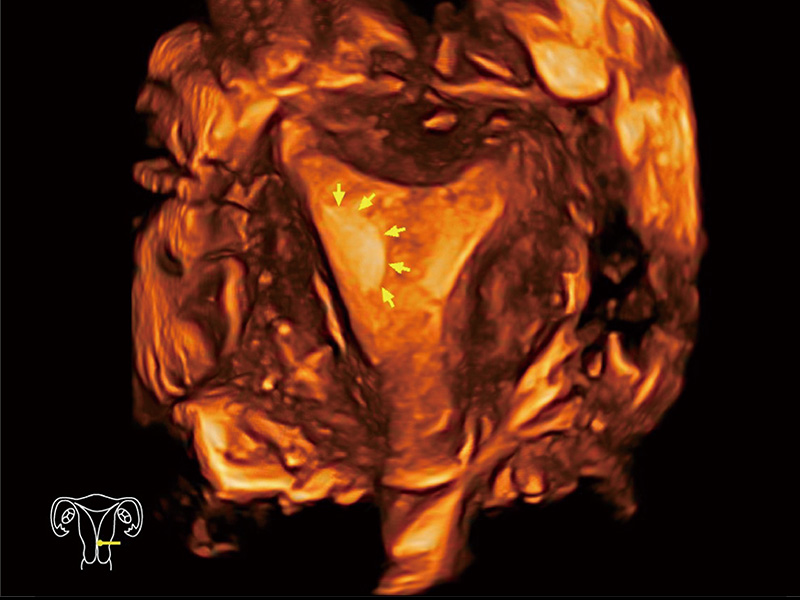

临床图

中央型宫腔粘连

单角子宫